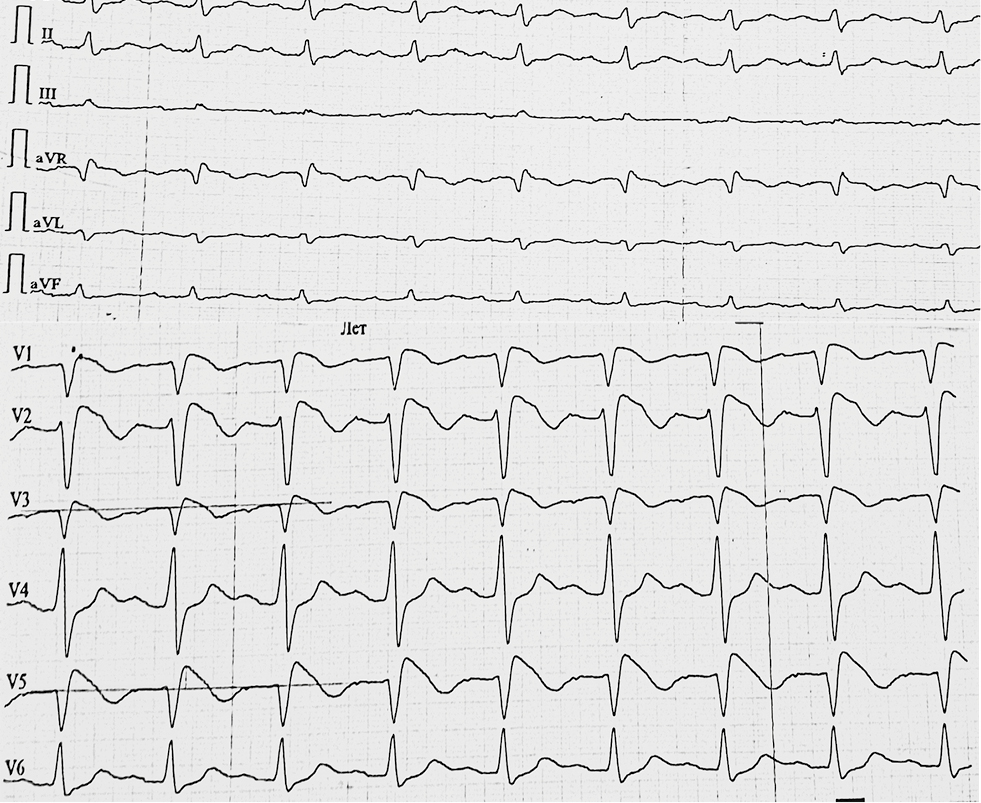

У пробанда № 641 (мужчина 38 лет) при выполнении рутинной ЭКГ зарегистрирован паттерн Бругада типа 2 (рис. 1).

Рис. 1. Электрокардиограмма в 12 отведениях пациентов № 598 и 641 с разными паттернами Бругада: а — паттерн Бругада тип 1 (coved), показывающий «сводчатый» подъем сегмента ST более 2 мм в более чем одном правом прекордиальном отведении, за которым следует отрицательный зубец Т; b — паттерн Бругада типа 2 (saddle-back), показывающий «седловидный» подъем сегмента ST более 2 мм в более чем одном правом прекордиальном отведении, за которым следует положительный зубец Т

Fig. 1. 12-lead electrocardiogram of patients (No. 598 and 641) with distinct Brugada patterns: a — Brugada pattern type 1 (coved), showing a “vaulted” elevation of the ST segment of more than 2 mm in more than one right precordial lead, followed by a negative T-wave; b — Brugada pattern type 2 (saddle-back), showing a “saddle-shaped” elevation of the ST segment of more than 2 mm in more than one right precordial lead, followed by a positive T-wave